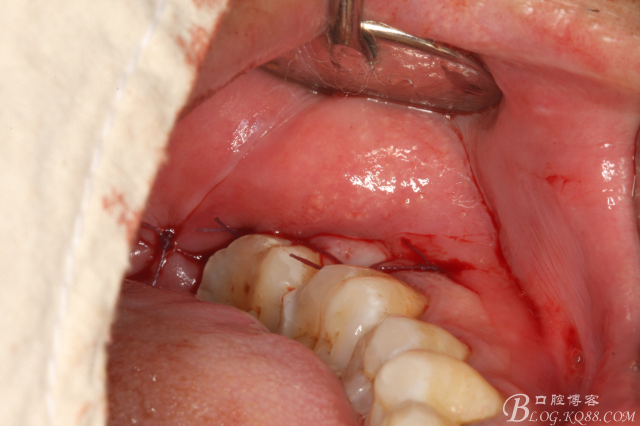

圖12.縫合